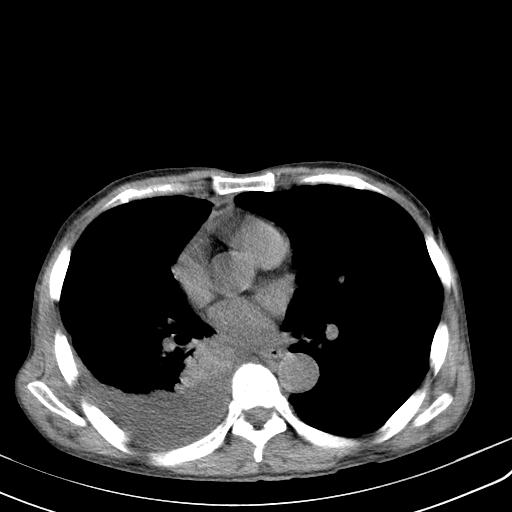

男性 75  咳嗽 一周前发热最高达39

右肺继发型tb并右侧tb性胸腔炎,右侧胸腔大量积液并右下肺膨胀不全,慢支肺气肿、多发肺大泡。建议抽胸水实验室检查并复查排除恶性在占位。

结核的基础上有纵隔淋巴结肿大,右侧有胸水,但右侧纵隔反而窄,说明有肺有不张。

再就是右下肺有块影,和不张混合,还是不能除外肺癌。

补充材料,患者2月份ct片大致正常,双侧胸腔积液,2月份抽胸水未发现ca细胞,现患者发热,痰多,各气管通畅,

1)右肺继发型肺结核。2)左肺胸膜下多发性肺大泡。3)右侧胸腔积液。